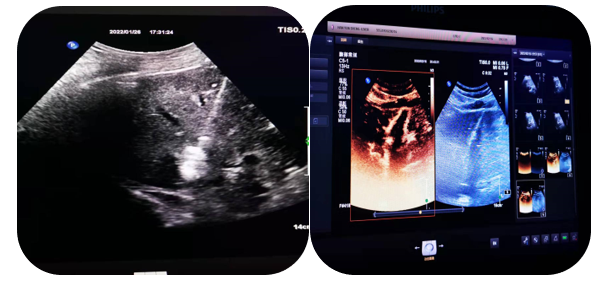

4.超聲介導下肝占位射頻及微波消融術

通過射頻電極發(fā)出高頻率射頻電流,電能使局部組織發(fā)生正負離子震蕩,并摩擦生熱達100°左右,熱能逐漸傳導至周圍組織,形成一個預定的球形或類球形的消融區(qū),腫瘤局部因高溫而發(fā)生凝固壞死。以達到和手術切除同樣的目的和效果。

5.超聲介導下囊腫硬化治療

局部麻醉患者清醒狀態(tài)超聲直視下穿刺針進入囊腫囊腔內(nèi)抽出囊液,注入硬化劑,手術時間短,損傷輕微,痛苦小,安全性高。